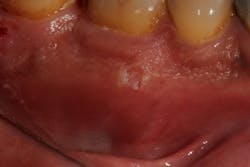

Figure 2: Major aphthous ulcer

- 10% to 15% of canker sores are major aphthous ulcers, usually larger than 10 mm in diameter, and can occur on both keratinized and nonkeratinized mucosa. These lesions can last two to eight weeks and may cause scarring in some cases (figure 2).